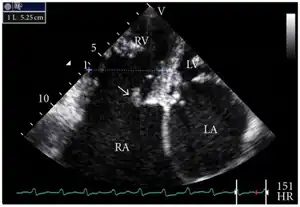

Definitive diagnosis is made by echocardiogram, which is capable of measuring both the presence and the severity of the TR, as well as right ventricular dimensions and systolic pressures.[12]

Transthoracic echo: enlargement of the right atrium in TR and mitral valve disease Transthoracic echo: TR (arrow)

Transthoracic echo: TR (arrow).jpg.webp) Echocardiogram: severe TR

Echocardiogram: severe TR